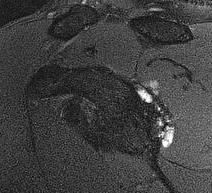

MRI

Posterior labral tears / bankart lesion

Posterior labral tears + cyst

www.boneschool.com/posterior-labral-cysts-suprascapular-nerve-compression